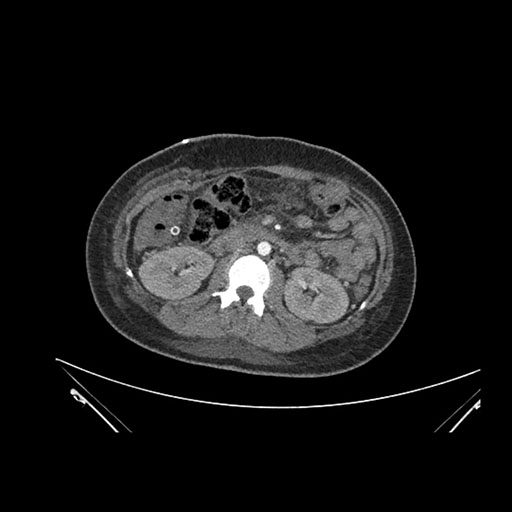

Axial Arterial

Axial Venous